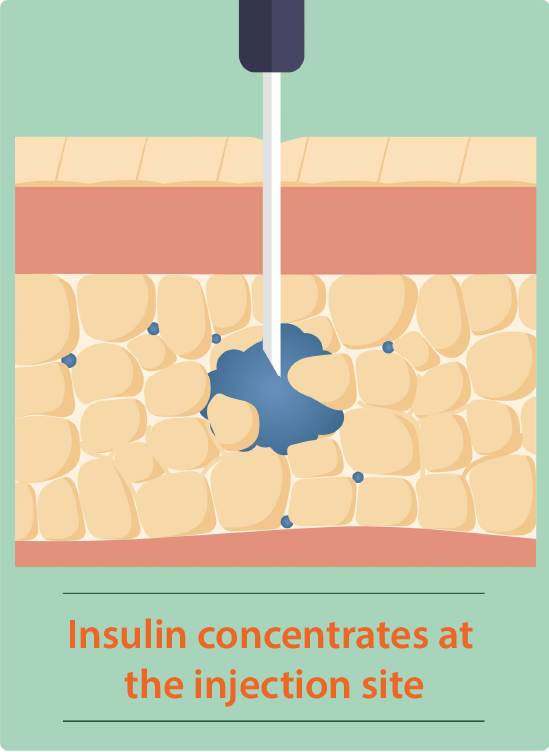

Traditional injection versus InsuJet™

Faster and effective absorption

- Optimized peak action

- Improved glycemic control

Applied to the skin, InsuJet™ delivers insulin in a thin jet injection that easily penetrates the skin, ensuring optimal distribution into the subcutaneous tissue.